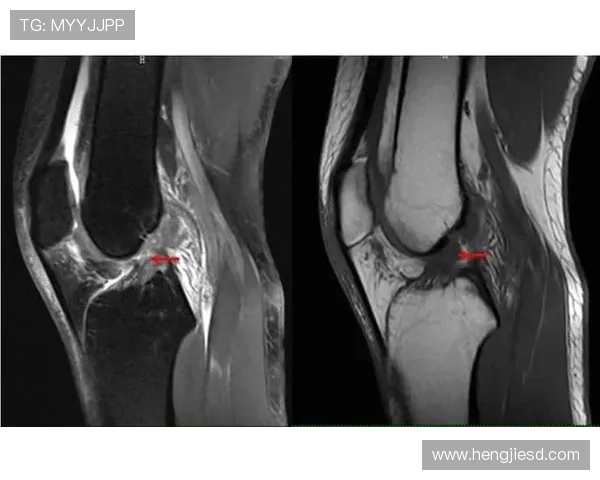

此外,治疗团队在跟踪过程中还定期对罗德里戈进行检查,及时了解膝关节的恢复情况。通过定期的影像学检查和体能评估,医生可以准确判断治疗进展,必要时调整治疗方案。这种细致入微的监控方式,帮助罗德里戈更好地应对康复过程中的各种挑战。